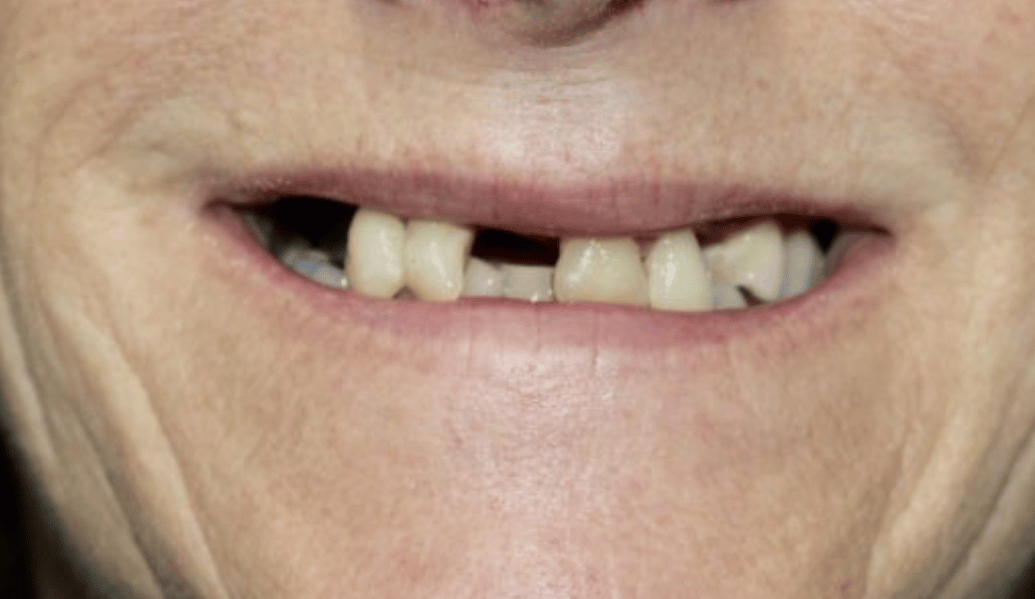

learn moreDelivering life-changing smiles and ensuring excellent dental health.